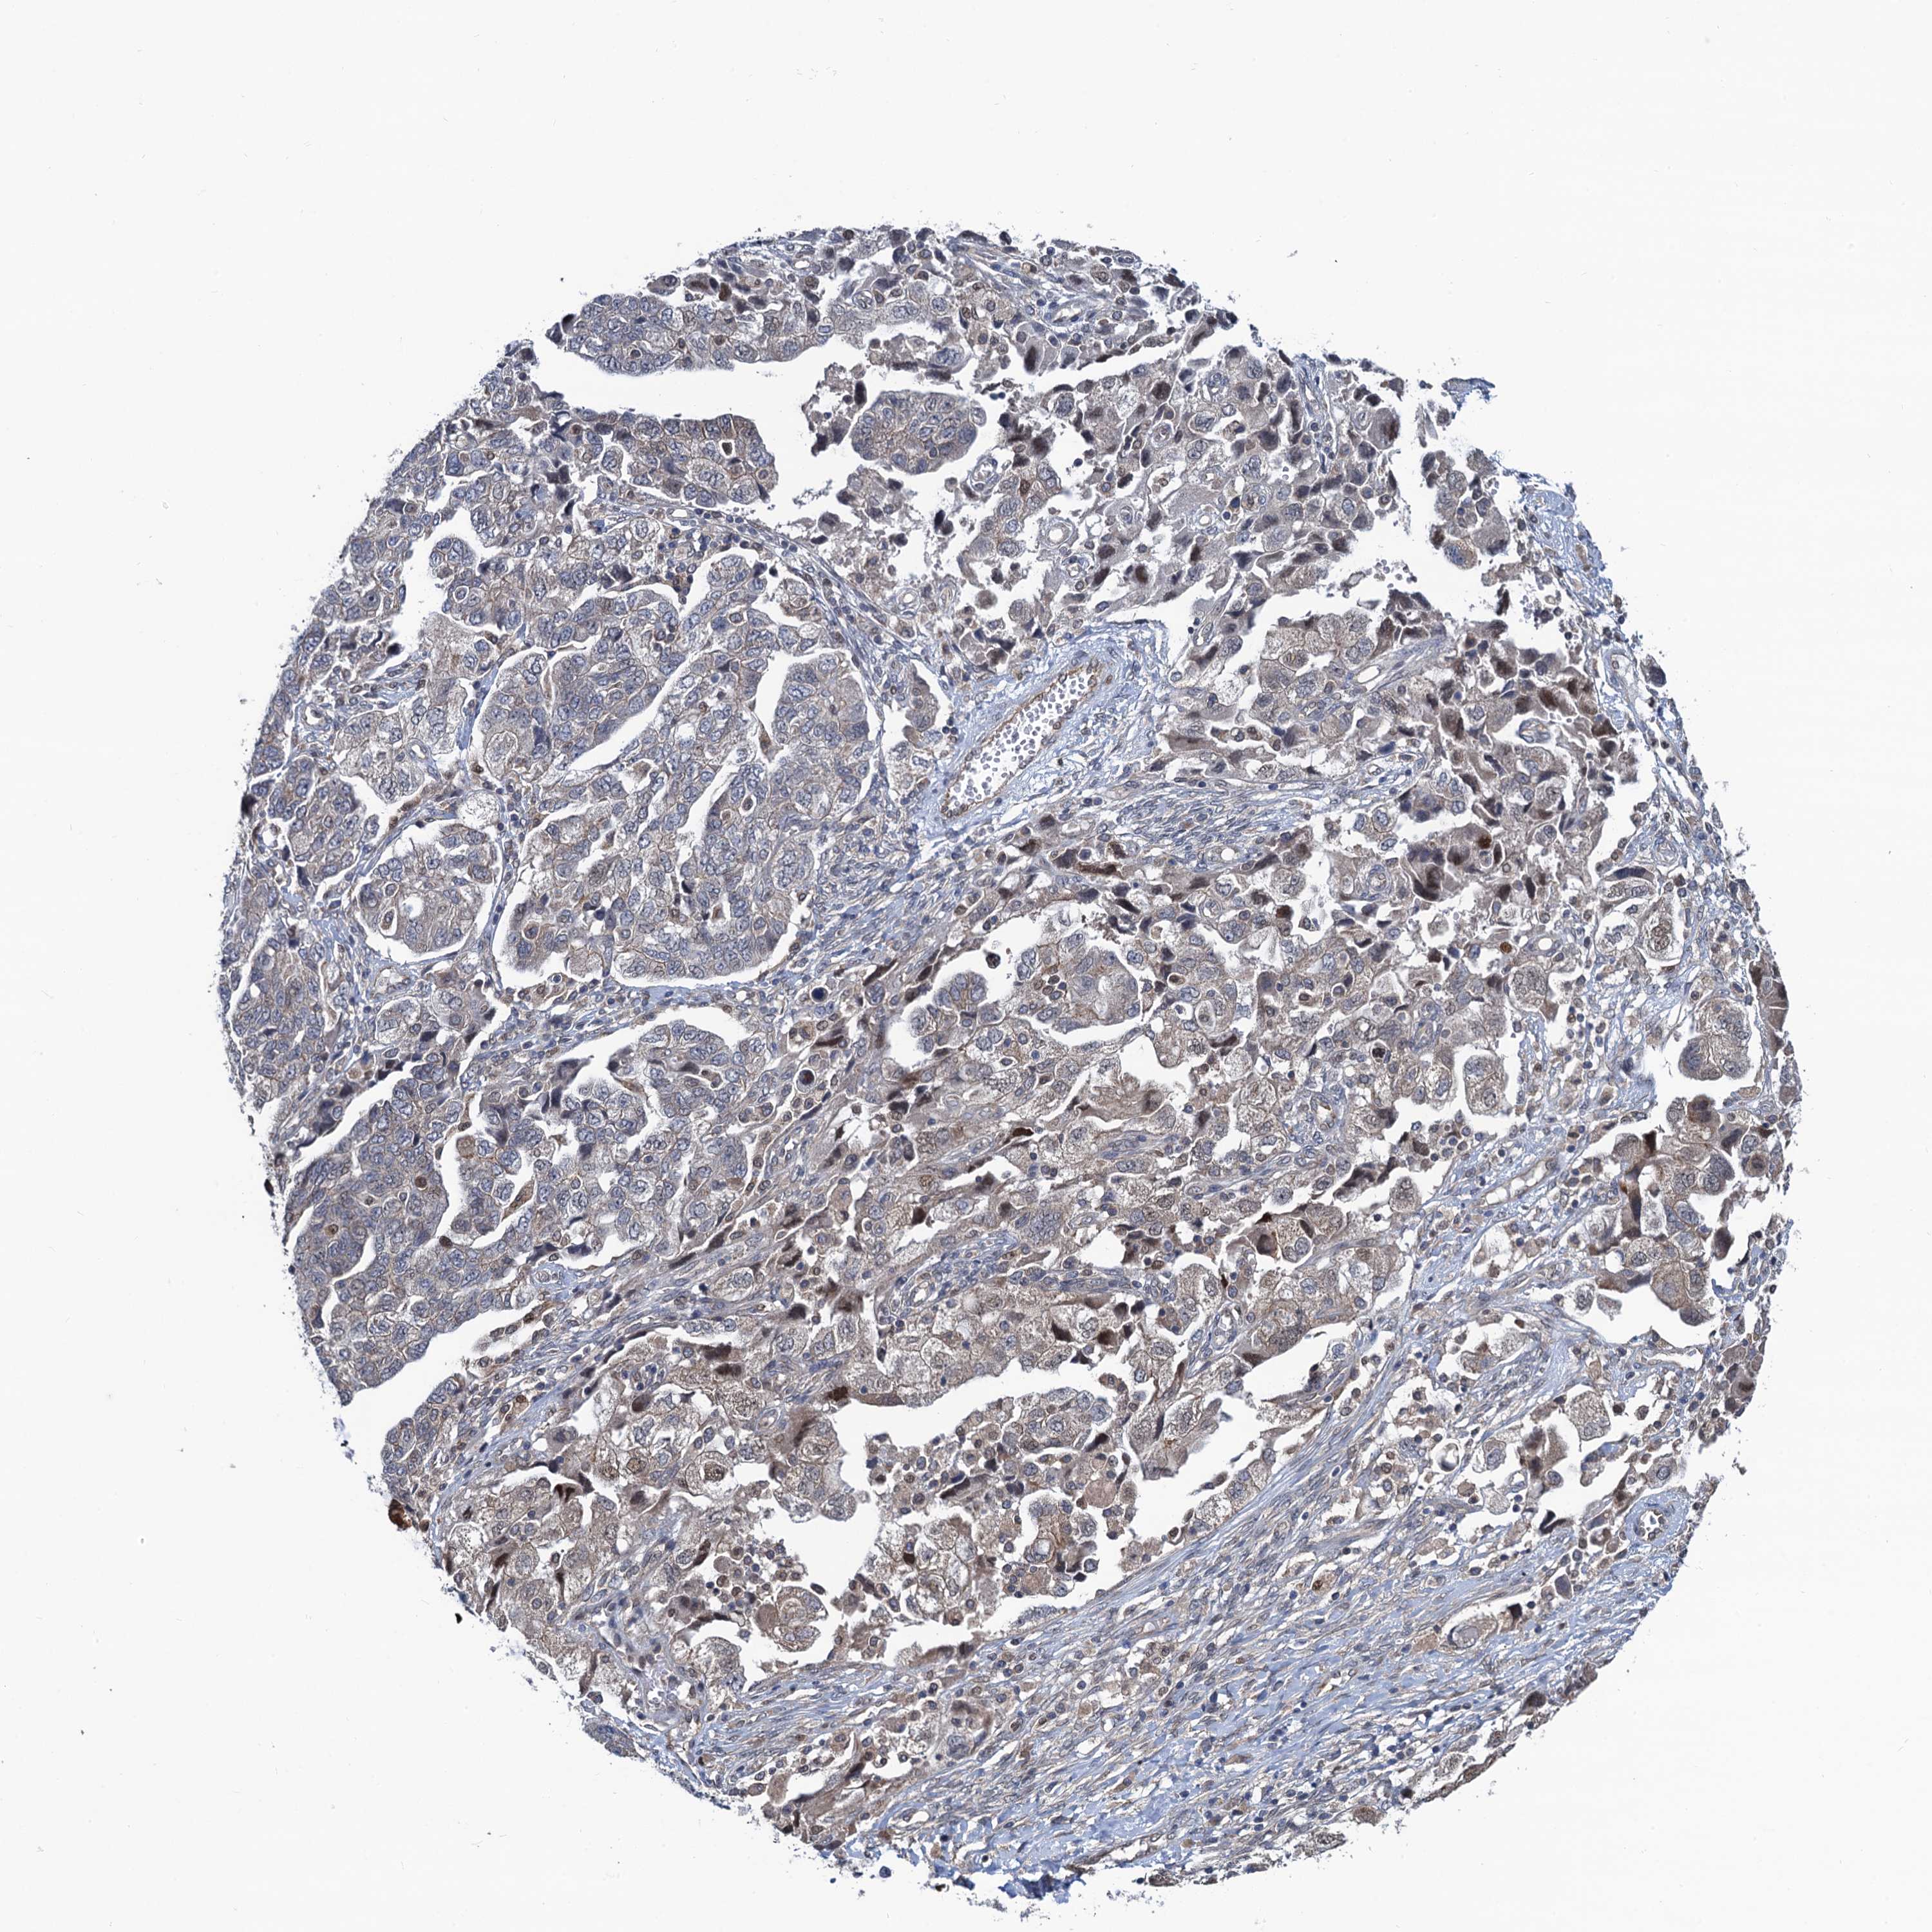

OVARIAN CANCER - Protein expressioni

A mouse-over function shows sample information and annotation data. Click on an image to view it in a full screen mode. Samples can be filtered based on level of antibody staining by selecting one or several of the following categories: high, medium, low and not detected. The assay and annotation is described here.

Note that samples used for immunohistochemistry by the Human Protein Atlas do not correspond to samples in the TCGA dataset.

Antibody stainingi

Antibody staining in the annotated cell types in the current human tissue is reported as not detected, low, medium, or high, based on conventional immunohistochemistry profiling in selected tissues. This score is based on the combination of the staining intensity and fraction of stained cells.

Each image is clickable and will lead to virtual microscopy that enables deeper exploration of all samples and also displays staining intensity scores, fraction scores and subcellular localization as well as patient and tissue information for each sample.

Antibody HPA041514

Staining

High

Medium

Low

Not detected

Intensity

Strong

Moderate

Weak

Negative

Quantity

>75%

75%-25%

<25%

None

Location

Nuclear

Cytoplasmic/membranous

Cytoplasmic/membranous,nuclear

Cystadenocarcinoma, serous, NOS

Carcinoma, endometroid

Cystadenocarcinoma, mucinous, NOS

Carcinoma, NOS